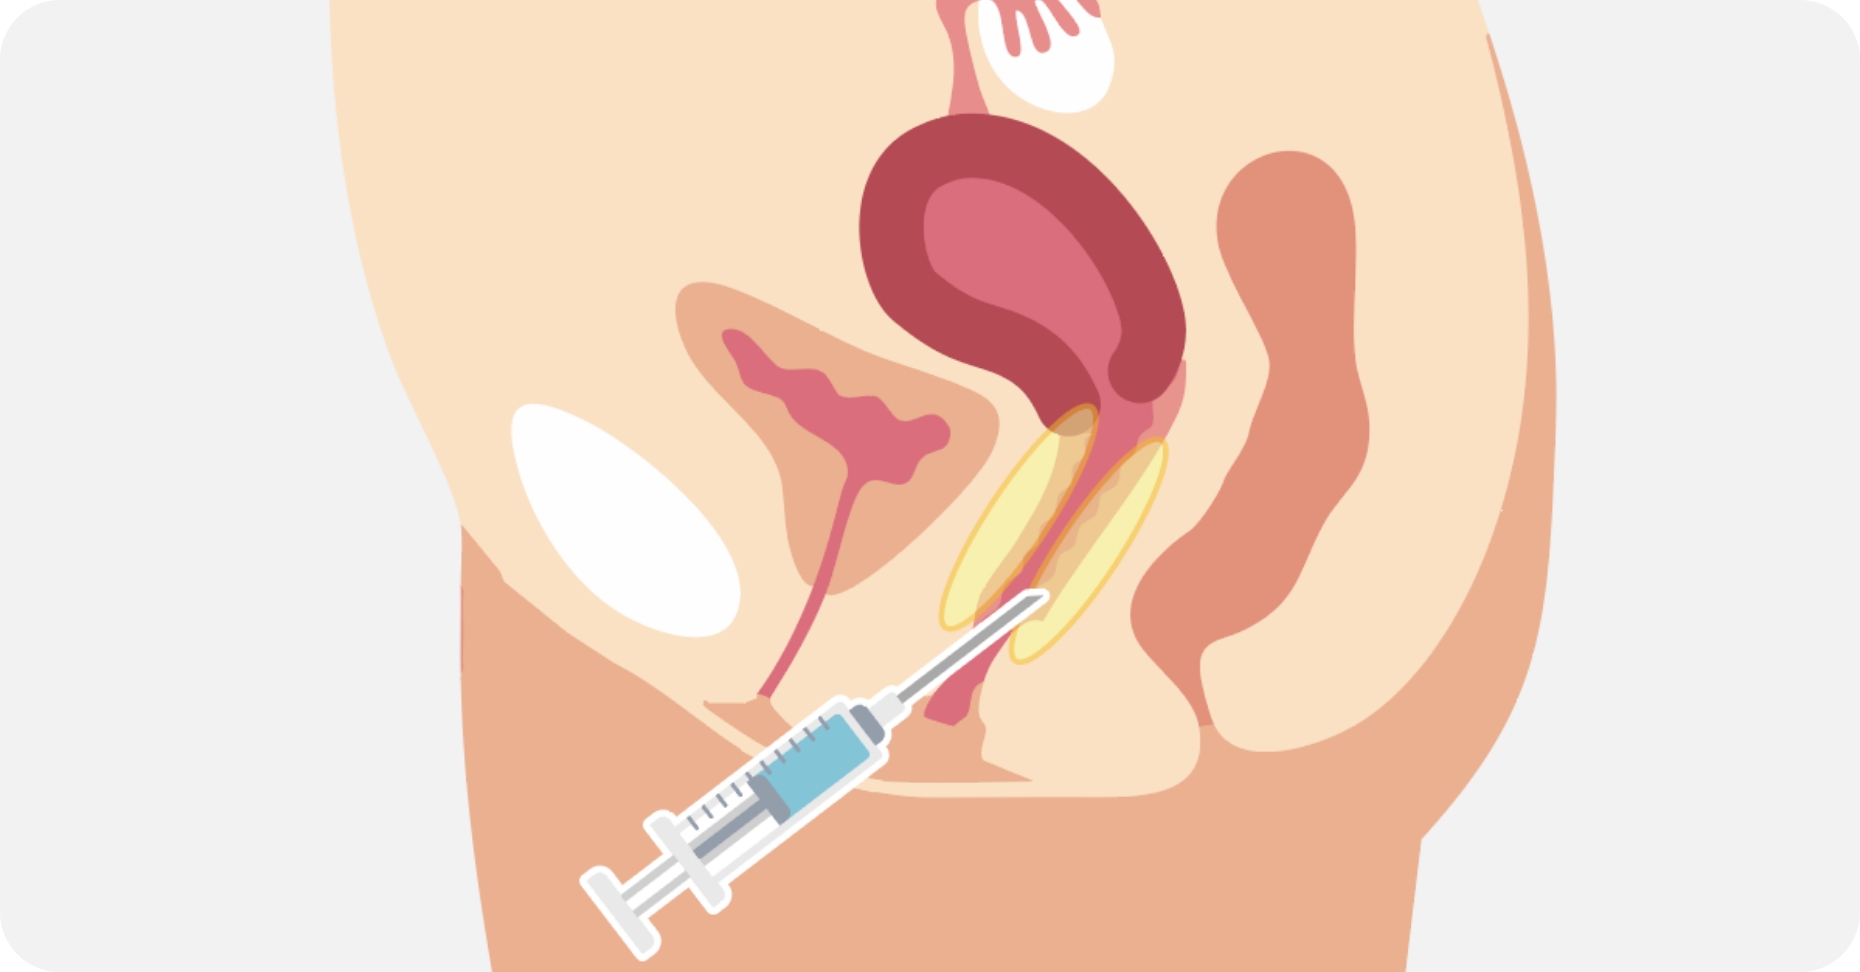

加齢や出産が原因で低下した膣圧を改善する治療です。ヒアルロン酸を注入する部位や量を変えることで、膣内の好きな部位を狭くし自由に膣圧を高めることが可能です。治療直後より効果が実感できます。性行為時の満足度を高めたり、女性として自信が持てたり、尿漏れを改善するなどの効果があります。当院では、膣治療を専門的に行なっているため、お悩みに合わせたカスタム注入が可能です。 ヒアルロン酸は少しずつ体内に吸収され、1.2年でなくなりますので、効果を持続させたい方は追加の注入が必要になります。 効果を持続させたい方は膣内の脂肪注入をご検討ください。

メスを使わない注入治療

切開を伴わず、ヒアルロン酸を膣壁に注入するだけの施術のため、身体への負担が少なく、初めての方でも受けやすいのが特長です。

① 部分注入(Gスポット周辺に注入)

Gスポット周辺にヒアルロン酸を注入し、膣粘膜に厚みをもたせる方法で、性感帯の膨らみを作ることで、刺激を感じやすくなる可能性があります。膣のゆるみよりも、快感度の向上を希望する方に適しています。

② 円周注入(膣の締まり感向上)

膣の周囲に均等に注入し、膣壁にボリュームをもたせる方法で、膣粘膜のハリを高め、膣のフィット感を向上させる可能性があります。

出産後に膣のゆるみを感じる方、膣のハリ不足が気になる方に適しています。

③ 多層注入(バランスのとれた名器形成)

膣の内〜外側にかけてヒアルロン酸をバランスよく注入する方法で、膣のハリと潤いを向上させ、より自然な仕上がりを目指す注入方法です。

膣のフィット感と潤いを同時にサポートしたい方に適しています。

④ 立体層状注入(名器形成を目的とした施術)

膣内の構造を立体的に整え、締まり感と性感向上を目的とした施術で、ヒアルロン酸を膣内に立体的に注入することで、ボリュームを調整し、より高い密着感やフィット感を目指します。

より強い締まり感やパートナーとの密着感を求める方に適しています。